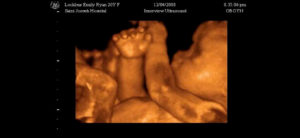

Вес ребенка на 34 неделе беременности может достигать 2,5 кг, а рост составлять 45 см. Очень интересно знать, как выглядит малыш на данном сроке. 34 недели беременности — это примечательный срок, когда малыш продолжает активно расти и развиваться.

С каждым днем кроха видоизменяется. На 34 неделе беременности УЗИ позволяет увидеть индивидуальные черты ребенка и даже определить, на кого он похож. Следует отметить такие явные изменения:

- На пальчиках полностью оформляются ноготки.

- Волосы на голове становятся гуще.